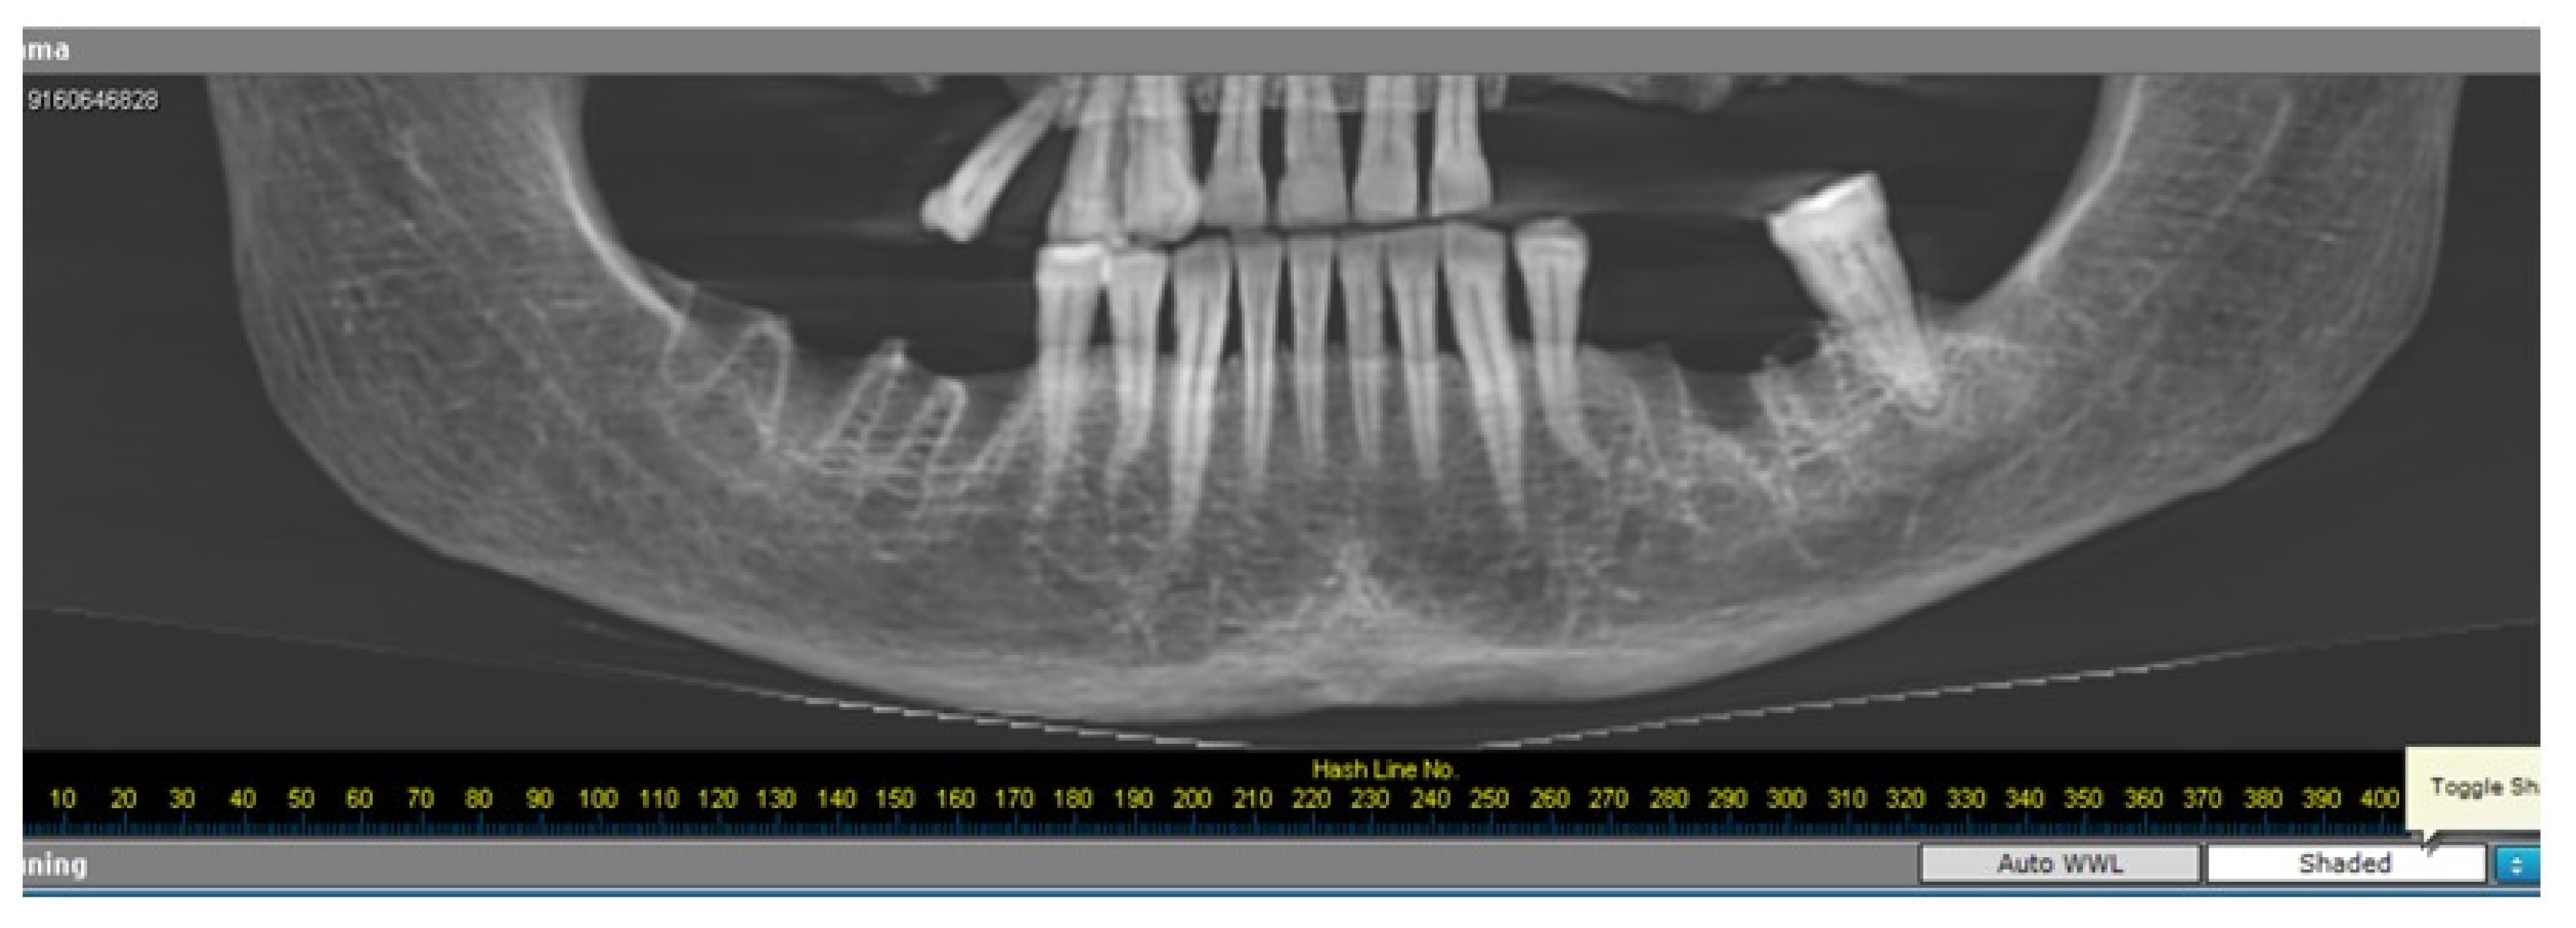

2.2. Radiomorphometric Assessments